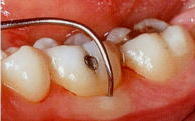

文献的にも、根分岐部の歯石は誰が、いかなる方法で取っても、取り残すことが証明されています。

| Matia, J.I.et al : Int.J.PRD 1986 | |